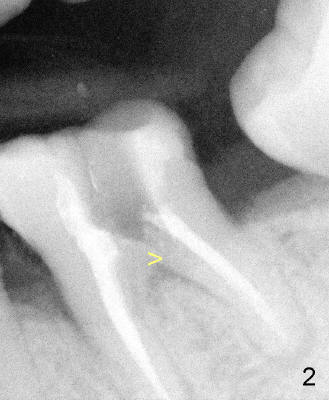

- Confirm placement of the ProRoot MTA root repair material with a

radiograph (Fig.3: M). If an adequate barrier has not been created, rinse the ProRoot MTA root repair material out of the canal and repeat the procedure